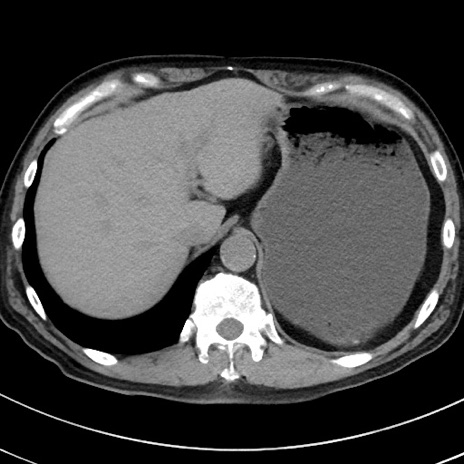

冠状断像

【症例】70歳代 男性

【主訴】腹痛・嘔吐

【現病歴】昨晩より、嘔吐・腹痛あり。今朝になっても嘔吐あり。来院。

【既往歴】心臓バイパス手術、開腹胆摘、腸閉塞

【身体所見】BP 107/71mmHg、HR 116/min、腹部:平坦、軟、下腹部に軽度圧痛あり。反跳痛なし。

【データ】WBC 15100、CRP 0.32